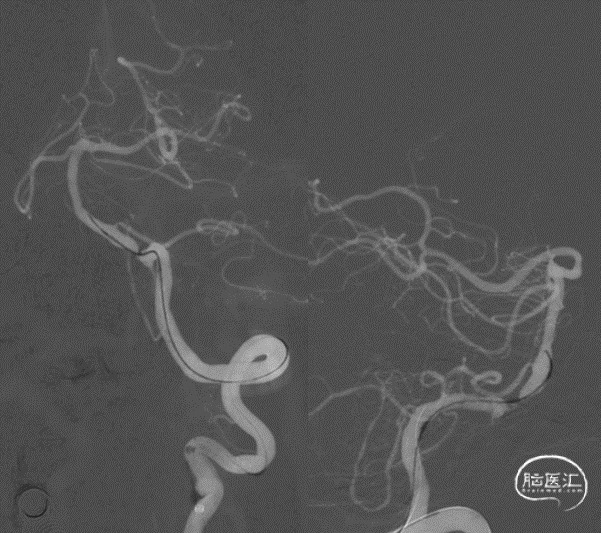

球囊扩张。

球囊扩张后狭窄有所改善。

支架顺利到达病变位置到位。

充盈球囊,释放支架。

支架释放后。